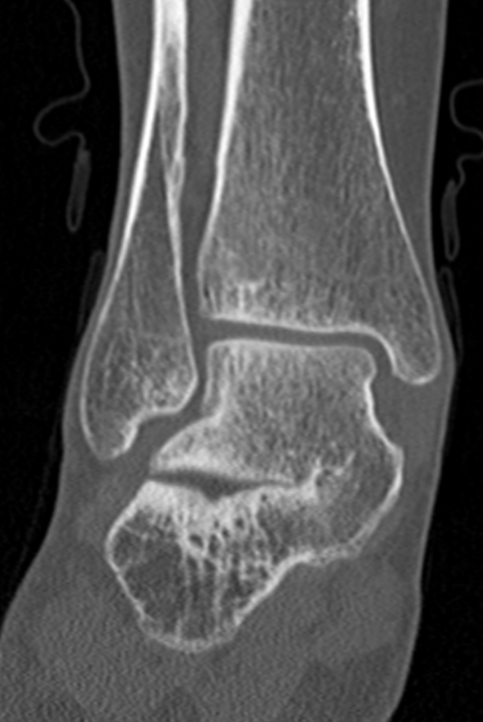

Talocalcanceal tarsal coalition